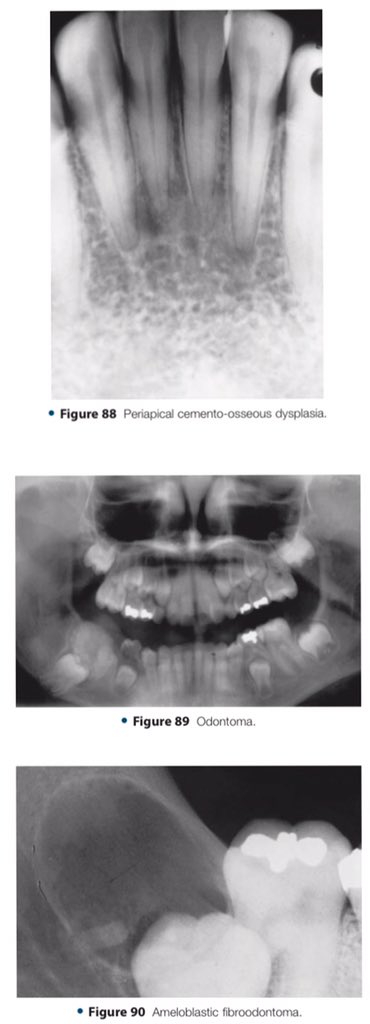

🔍| Differential Diagnosis Approach to Jaw Lesions. #aboutDent